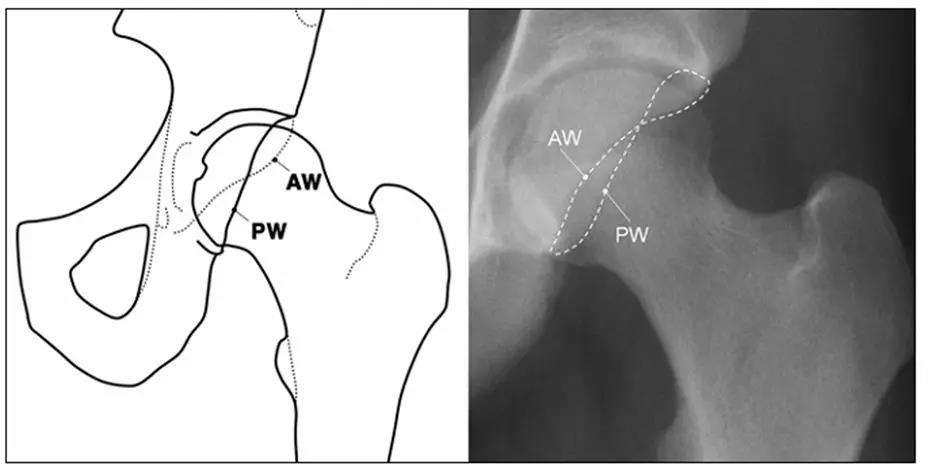

- 正常髋关节X线表现。

- 中心边缘角(LCE角)正常范围为25一39;髋臼指数(AI)正常值>0;挤压指数(E/A+E)正常值<25%。

- IIL:髂坐线;AW:髋臼前壁缘;PW:髋臼后壁缘;A为股骨头被髋臼覆盖部分的宽度;E为股骨头未被髋臼覆盖部分的宽度;F为髋臼窝线。

髋臼过深,髋臼窝线位于髂坐线内侧。

- 髋臼窝线位于髂坐线内侧。

- LCE>39°时,提示髋臼过渡覆盖。

- 正常髋臼指数(AI)为正值,AI为0或负值提示髋臼过深。

- 髋臼过深:髋臼线位于髂坐线内侧。

- 髋臼突出:更内侧(成人:男性>3mm,女性>6mm;儿童:男性>1mm,女性>3mm。)

- 髋臼前突,股骨头与髂坐线相交